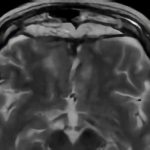

症例 '17年1月

No.

2

※ 画像をクリックすると拡大表示します。症例No.は平成29年から起算しています。

年_番号

手術年月

患者年齢

’17_2

'17年1月

60代

病名

術式

備考

嗅溝部髄膜腫

頭蓋内腫瘍摘出術

断層撮影

手術前

1

手術前2

手術後